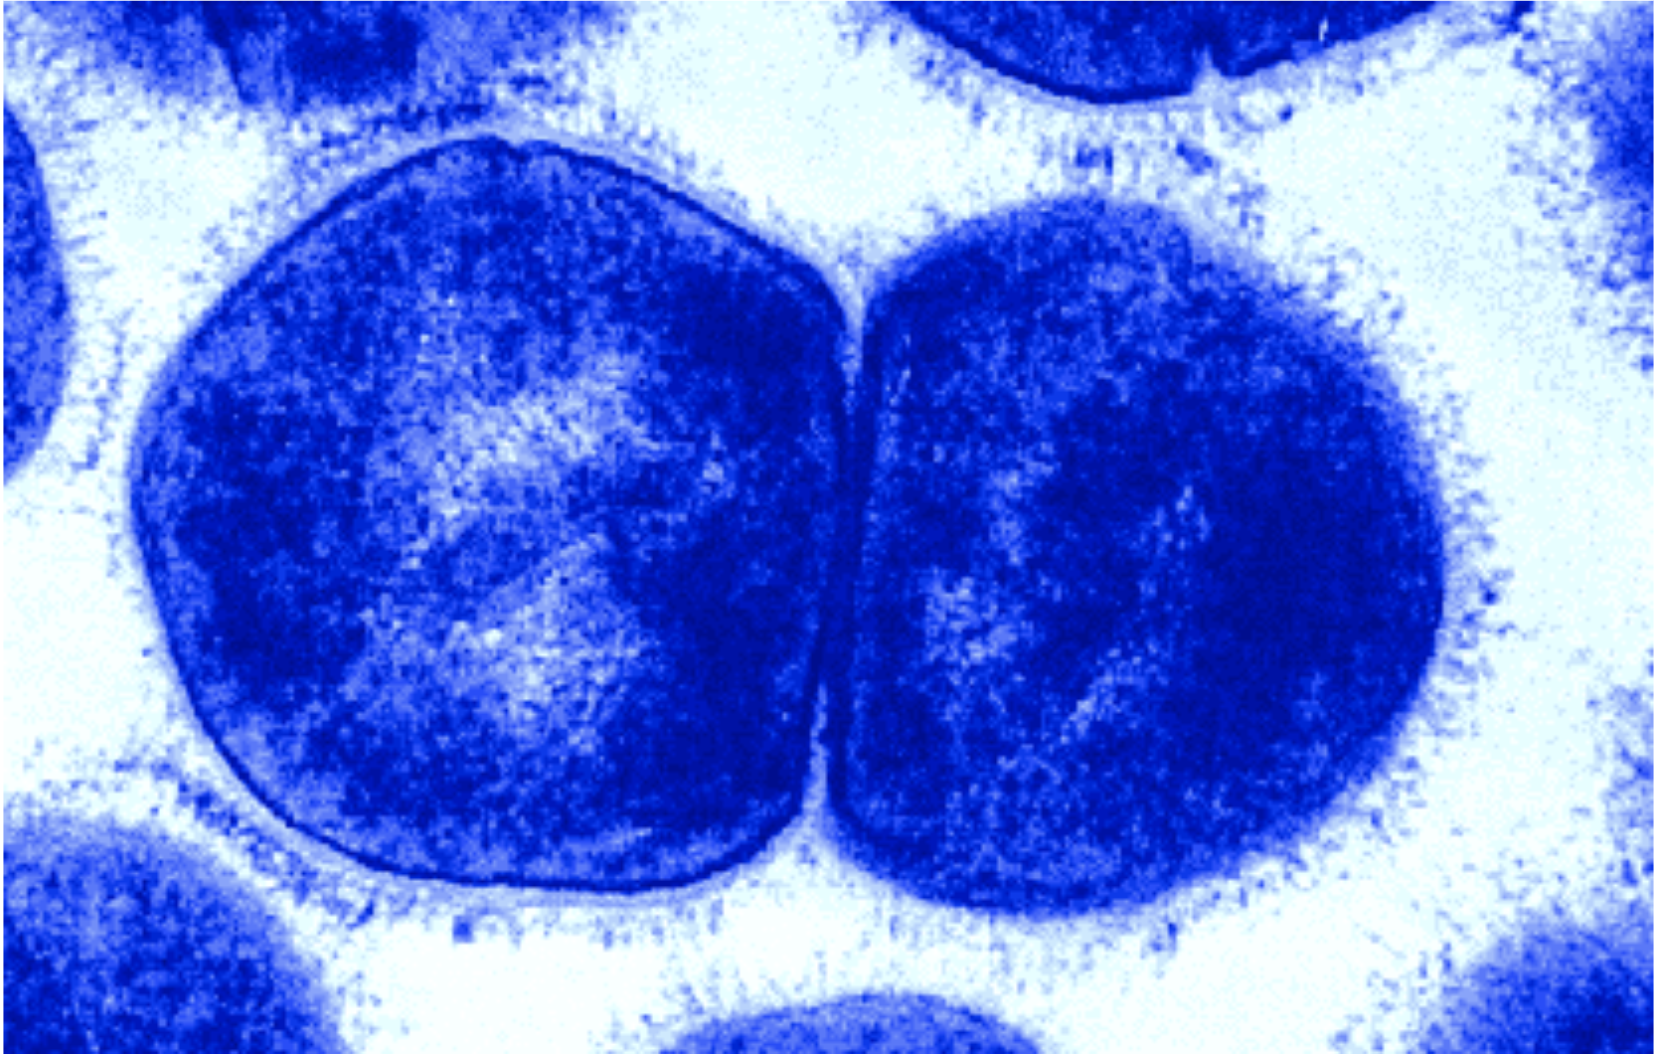

The genus Streptococcus is comprised of a wide variety of both pathogenic and non-pathogenic (commensal) gram-positive bacteria which are found to inhabit a wide range of hosts, including humans, horses, pigs and cows. Within these hosts, streptococci are often found to colonize the mucosal surfaces of the mouth, nares and pharynx. However, in certain circumstances, usually under disease conditions, they may also inhabit the skin, heart or muscle tissue.